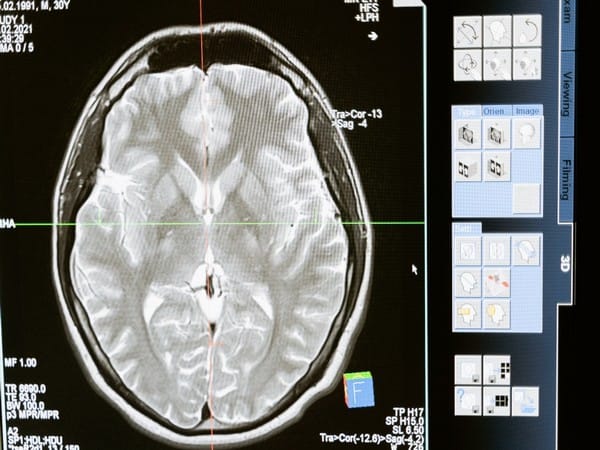

The subthalamic nucleus is a tiny grouping of cells that is part of the basal ganglia, which is a key circuit in controlling movement. The basal ganglia takes initial motor commands generated in the brain and either amplify or halt specific parts of those commands as they pass from the central nervous system to the spinal cord.

“You can think of the subthalamic nucleus as the core region in this ‘halting’ of extra, unwanted components of compound movements, as it is the last relay station before the output nuclei of the basal ganglia, which then communicates these commands to the wider motor system,” says Jan Wessel, associate professor in the Department of Psychological and Brain Sciences at Iowa and the corresponding author on the study.